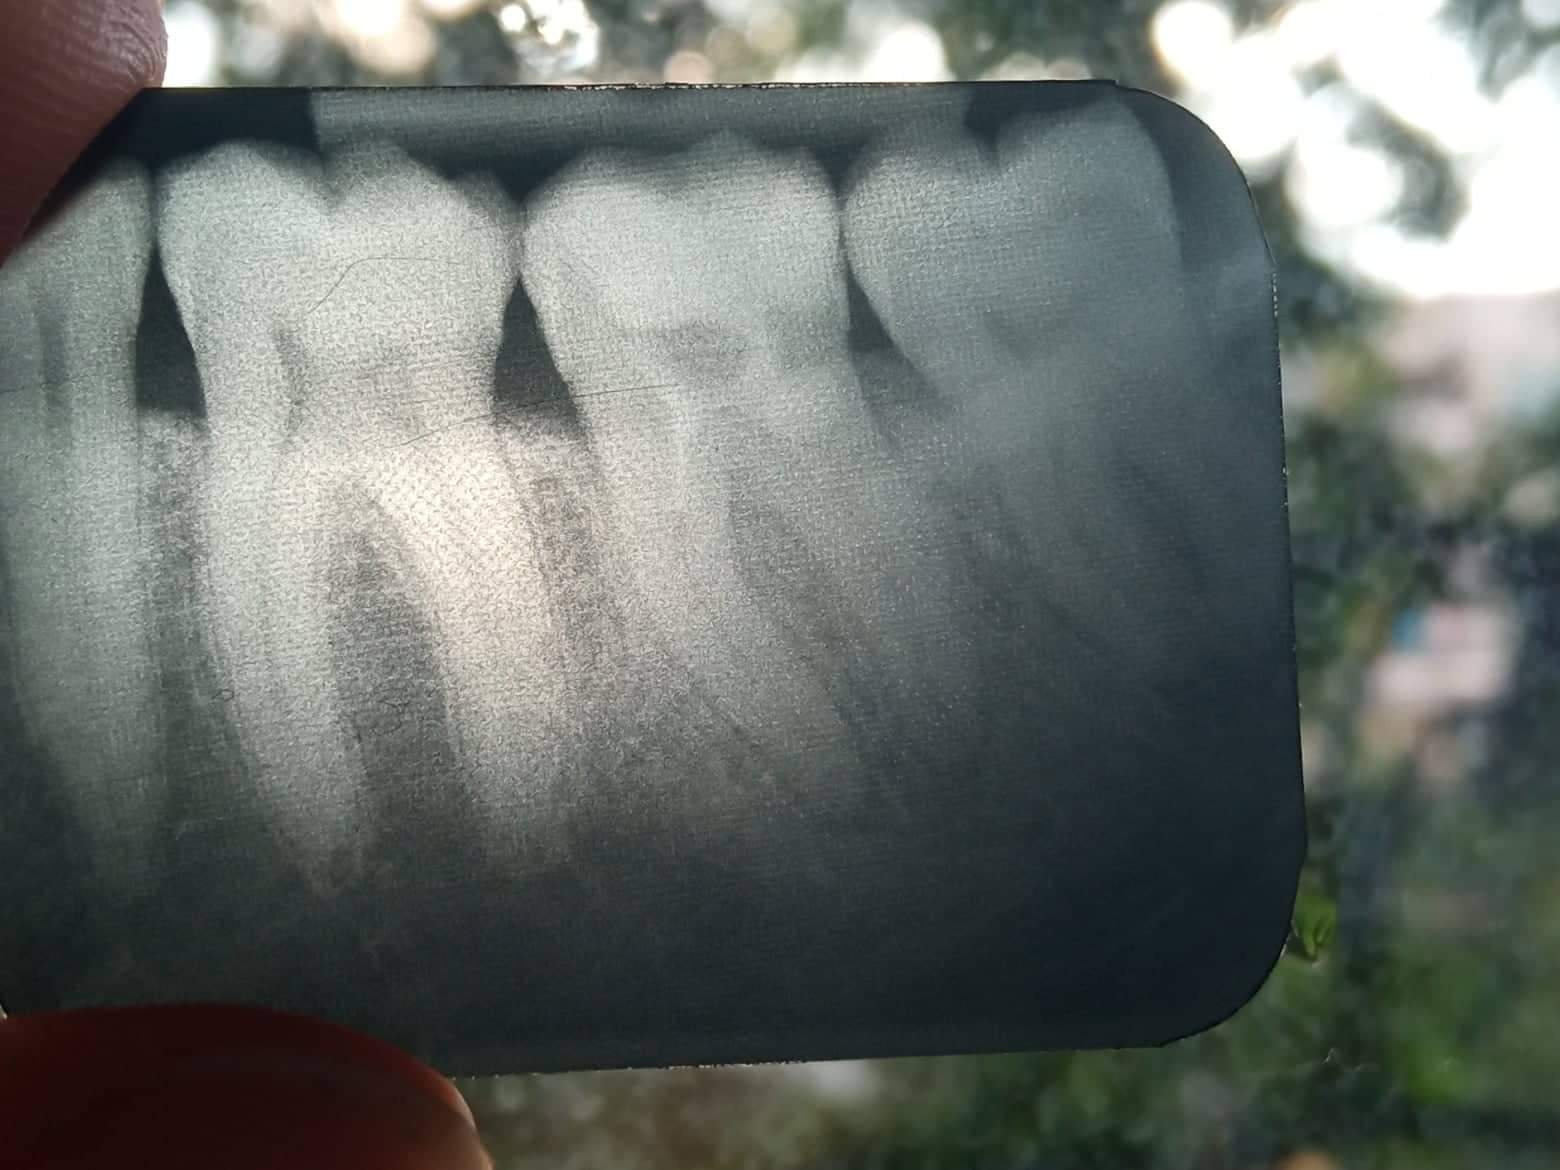

По-добре ли е да се постави имплант вместо кореново лечение и корона за умъртвен зъб?